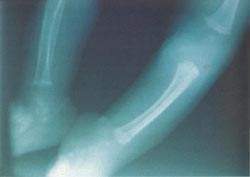

Radiografía Baby Scan: Condrodisplasia punctata y acortamiento de húmeros (1). Inicio (Fotografías 3 y 4) y Rx a los 9 m persiste acortamiento de húmero y fémur, pero ya no se evidencia calcificaciones epifisiales en granulado en cabeza de húmero. Biopsia de piel: Hiperplasia psoriasiforme de epidermis y estrato córneo homogenizado y eosinófilos. Ausencia de granulosa sugestivo de Ictiosis vulgar.

Condrodisplasia punctata. Se presenta en variedad rizomélica en niños de 6 meses de edad, cuyos padres son consanguíneos en primer grado. Se reportan las alteraciones cutáneas distribuidas a nivel de flexuras y zonas acrales; asímismo, acortamiento de miembros (rizomelia) y calcificaciones en zonas epifisiales. La condrodisplasia punctata, rizomelia, es una enfermedad de Conradi.